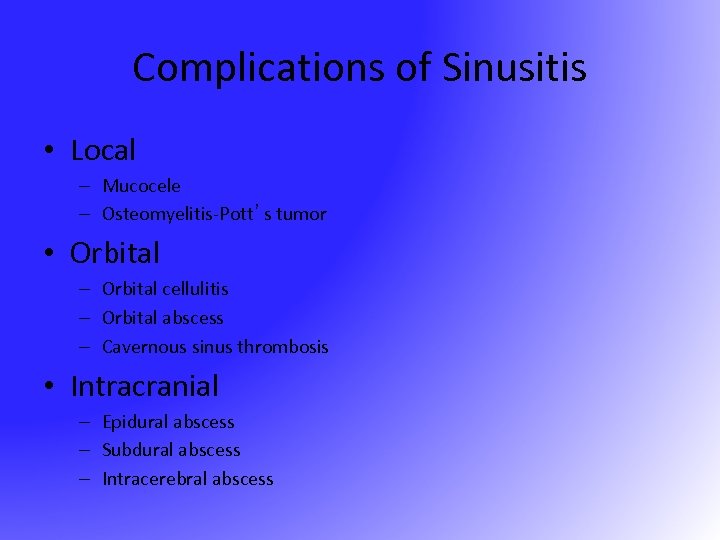

Complications of Sinusitis • Local – Mucocele – Osteomyelitis-Pott’s tumor • Orbital – Orbital cellulitis – Orbital abscess – Cavernous sinus thrombosis • Intracranial – Epidural abscess – Subdural abscess – Intracerebral abscess

Complications of Sinusitis • Local – Mucocele – Osteomyelitis-Pott’s tumor • Orbital – Orbital cellulitis – Orbital abscess – Cavernous sinus thrombosis • Intracranial – Epidural abscess – Subdural abscess – Intracerebral abscess